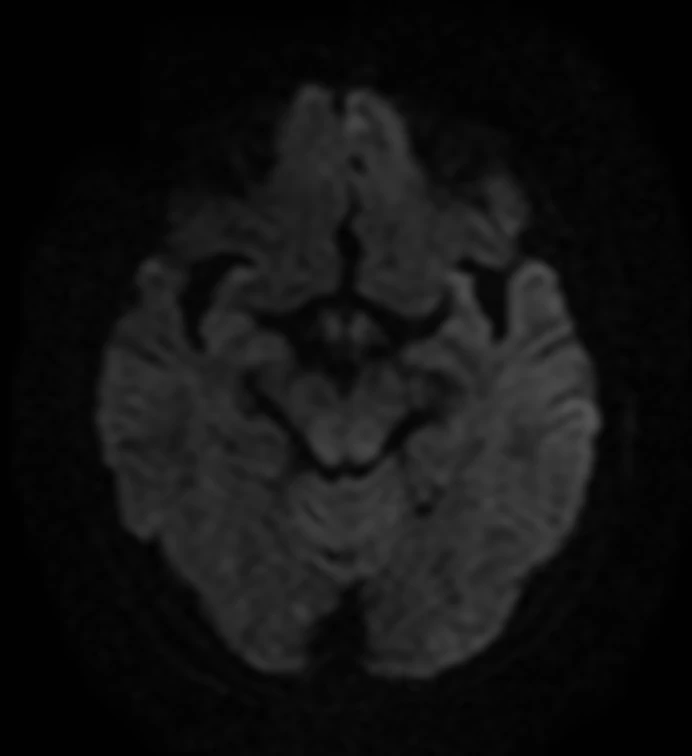

Мужчина 35 лет, месяц назад упал с высоты двух метров, сейчас не полностью ориентирован в месте и времени. Типичная (кроме мозжечка справа) картина травматического аксонального повреждения 3 степени (с поражением ствола). Множественные мелкие точечные и линейные микрокровоизлияния, вокруг части из них видны глиоз/отек. А вот в мозжечке, реально, нечасто такое увидишь. Но бывает. Типа, как вот здесь: